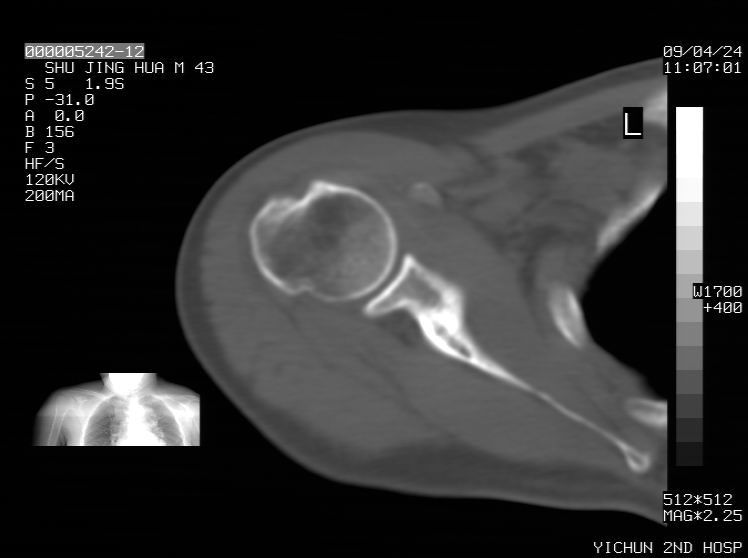

标题: CT19569:请会诊,女50岁,右肩疼痛数月 [打印本页]

标题: CT19569:请会诊,女50岁,右肩疼痛数月

考虑骨软骨瘤可能

考虑骨化纤维瘤

多考虑骨化性纤维瘤 。

钙化性肌腱炎

是指钙盐沉积在变性肌腱中的一种无菌性炎症,常见于肩关节的肩袖肌腱,引起肩部疼痛和活动受限。分为急性和慢性两种类型,急性型有肩关节突然出现急性疼痛的发作史,夜间可痛醒。

以下是引用余辉在2009-4-24 15:24:00的发言:[br]考虑钙化性肩周炎,肱二头肌长腱或相应附属组织钙化